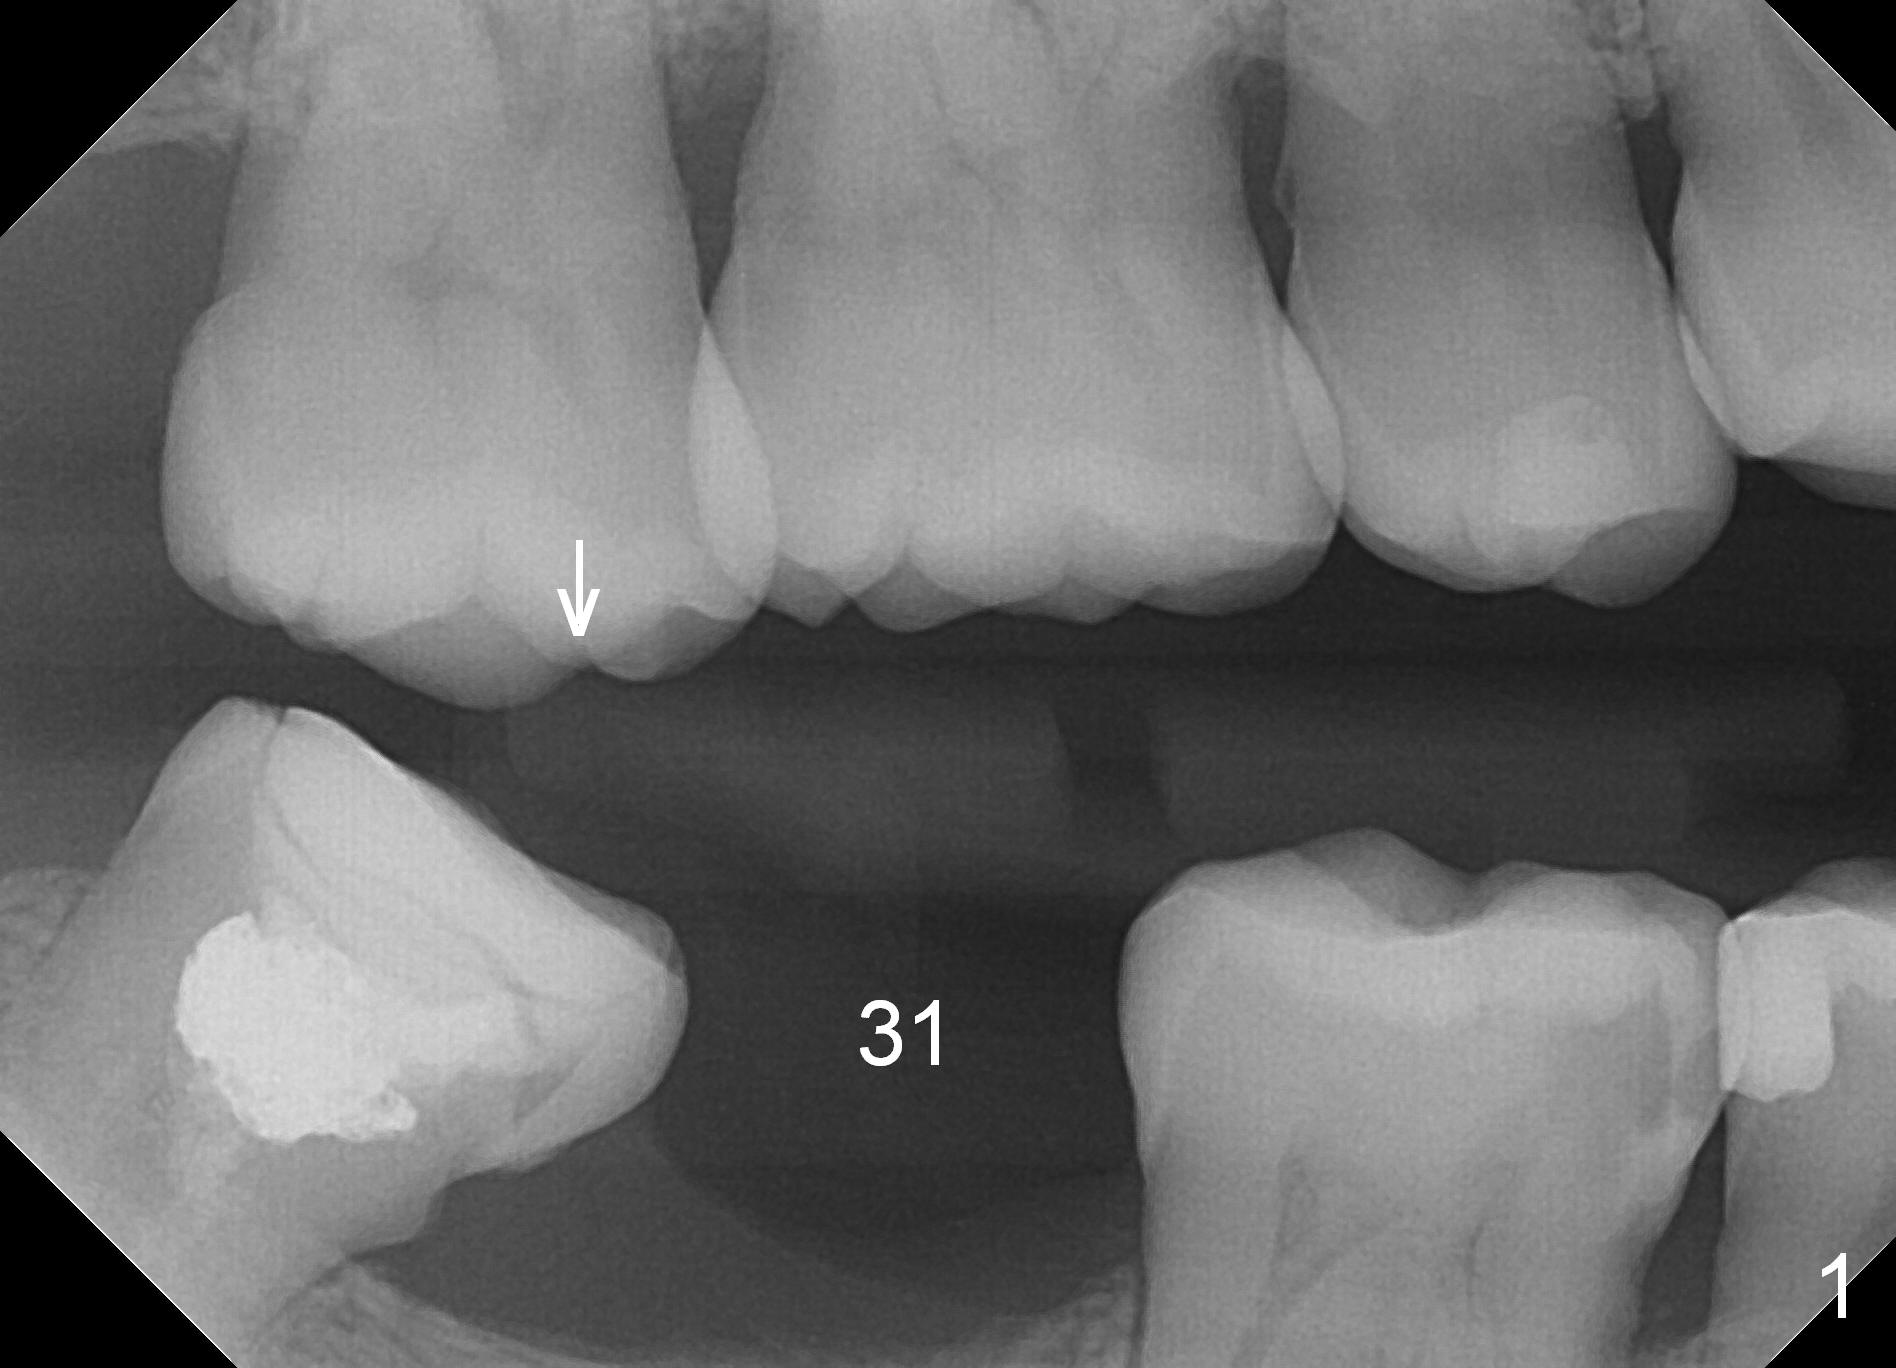

A 39-year-old man presents to office for #19/20 composite redo. After discussion he agrees to restore #31 with implant (Fig.1-3). He worries about bone loss (buccolingually) because of 8-year loss of the tooth. Fortunately the mesiodistal space is less than 8 mm (Fig.3). A 4 mm IBS implant (Titanium V (Bicon as well) stronger (not easily break) than Titatium IV (Tatum, DIO)) should be able to sustain mastication if the tooth #32 is not extracted. After local anesthesia, remove calculus in the mesial surface of #32 (Fig.2 ^). Also prepare for MO composite at #30.